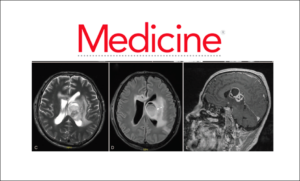

A brain abscess was found and surgically drained. Matrix-assisted laser desorption ionization–time-of-flight mass-spectrometry and heat shock protein 65/16S-23S rRNA gene intergenic spacer genotyping from the…